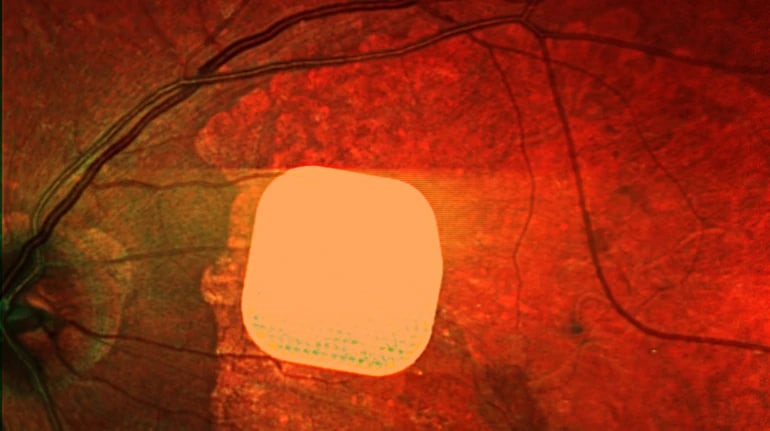

Британські лікарі з лондонської клініки Moorfields Eye Hospital спільно з колегами з інших європейських медичних закладів протестували новий електронний імплант Prima, який може допомогти пацієнтам з віковою сліпотою, спричиненою макулодистрофією. Цей мікрочип встановлюють під сітківку ока пацієнта, що дозволяє частково відновити їх зір. Під час операції також під’єднують систему окулярів доповненої реальності, яка допомагає зчитувати зображення та передавати його на мікрочип. У дослідженні взяли участь 38 пацієнтів із важкою втратою зору, і після імплантації більшість з них знову змогли розрізняти літери, цифри та слова. Лікарі вважають, що ця технологія може значно покращити якість життя людей з важкими зоровими порушеннями, дозволяючи їм повернути здатність читати та бути більш незалежними.